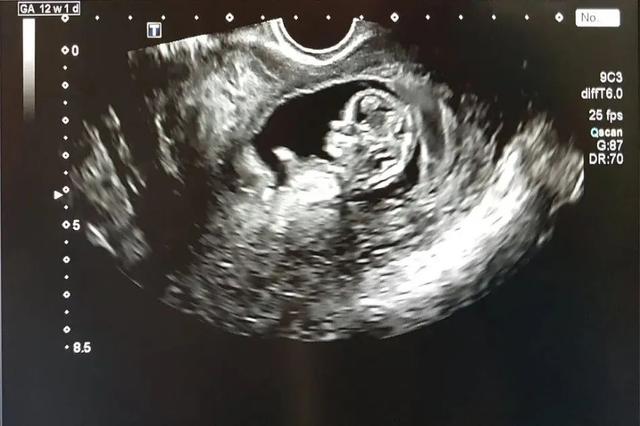

对于妊娠糖尿病我应该是非常有发言权了,因为我两次怀孕都被确诊。我孕前体重只有96斤,身体一直很健康也没有糖尿病家族也没有糖尿病史。第一次怀孕时因为前四个月孕吐严重,所以不爱吃饭只喜欢吃水果,后期是热带水果,摄入了过多的糖份,体重一路飙升,等到做糖耐的时候就被确诊为妊娠糖尿病。

本人95宝妈,怀孕期间孕吐到5个月,后面检查又有妊娠糖尿病。前期后期控糖很重要。

我就是在孕30周的时候有早产迹象,保胎1个月。保胎经历下次说。

37周多我生产的,医生跟我说,由于我有妊娠糖尿病,宝宝出生有可能有新生儿低血糖,要住保温箱,还有我生产的各种风险和并发症。

还好我孕期控糖控得比较好,宝宝出生一切正常。